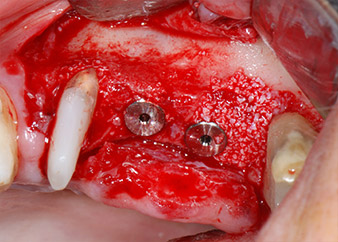

Имплантите (Restore, Keystone Dental, диаметър 3,75 mm, дължина 8.0 mm) са поставени с имплантологичен мотор

(Фиг. 11 и 12).

Дефицитът на кост около имплантите, от мезиален аспект на зъб 27 и около букалния корен на зъб 24, е запълнен с ксеногенни костозаместващи частици и покрит с абсорбираща колагенова мембрана (Bio-Gide, Geistlich Biomaterials) за GBR аугментация (Фиг. 13 и 14).